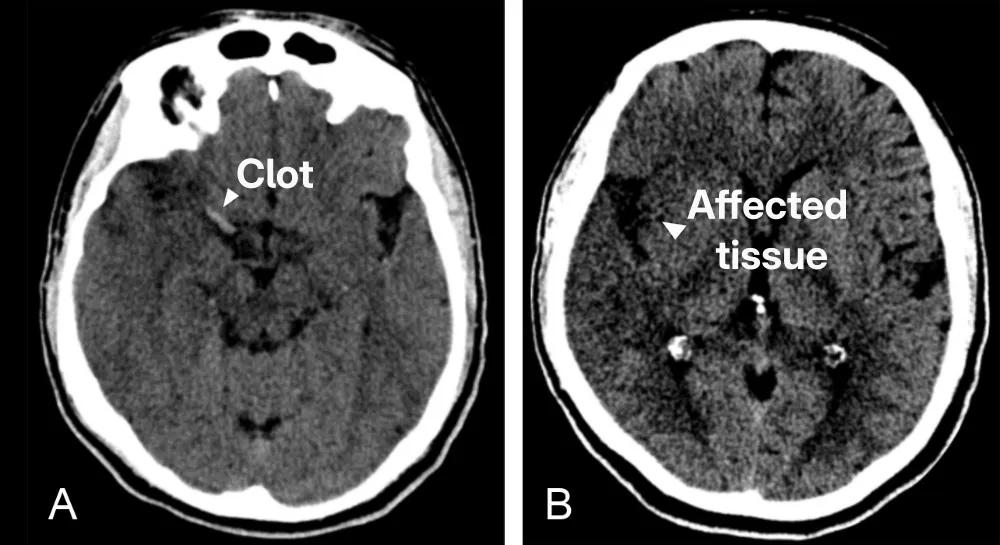

Computed Tomography (CT) Scan

A CT scan of the brain is often the first imaging modality used in suspected stroke cases because it is quick, affordable, and widely available. While CT is excellent for excluding haemorrhage, it has limited sensitivity in detecting an ischaemic stroke in the acute setting. Over time, however, the effects of stroke become more pronounced and obvious on CT scans (fig. 1).

Figure 1: CT scan of the brain of a patient with stroke. (A) Shows the bright clot. (B) Shows the darker region where the brain has not received enough blood.